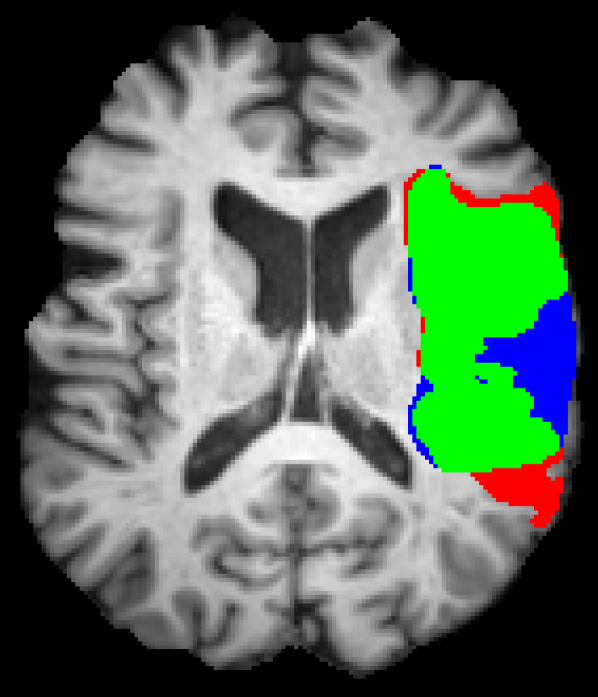

Figure 5 shows qualitative results of four representative segmentation examples from the proposed method. In general, the majority of the lesion is correctly segmented with minor border and small hole inaccuracies as seen in cases 11 and 26. Other less typical errors include under or oversegmentation of the lesion, as seen in case 2 where false positives are found on the upper part of the lesion. In the example of case 15, the lesion is undersegmented due to a confounding unusual appearance of some parts.

Refer to caption

(a) Case 2

(b) Case 11

(c) Case 15

(d) Case 26

Figure 5: Output segmentation masks of representative cases from the training images of ISLES 2015 SPES dataset. On all images, true positives are denoted in green, false positives in red and false negatives in blue.